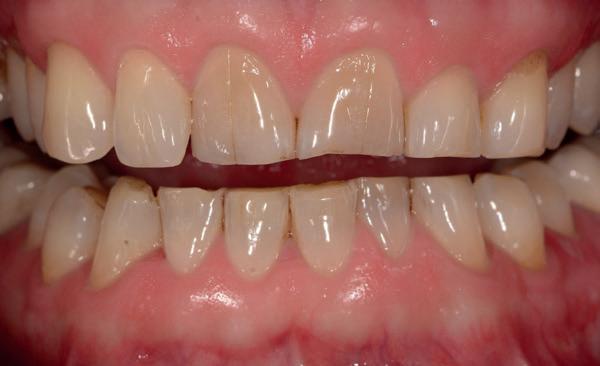

sportdranken) of van binnenuit (maagzuur, reflux, eetstoornissen). Glazuur verliest zijn hardheid, en eenmaal verzwakt, is het extra gevoelig voor andere slijtagevormen. Klinisch zie je gladde, glanzende oppervlakken, cupping in de molaren en doorschemerend glazuur (afbeelding 1).

2. Attritie: Attritie ontstaat door tand-op-tandcontact, zoals bij bruxisme. Het leidt tot vlakke kauwvlakken en korter lijkende tanden. Hoewel enig attritie fysiologisch is bij het ouder worden, wordt het pathologisch bij overmatig knarsen of klemmen. Je ziet dan slijtvlakken die spiegelbeeldig op elkaar passen (afbeelding 2).

3. Abrasie: Abrasie is slijtage door mechanisch contact met externe factoren, zoals foutief poetsen of nagelbijten. Meestal zie je wigvormige defecten ter hoogte van de tandhals. De laesies zijn vaak glanzend en gepolijst, maar kunnen ook verkleurd zijn. Abrasie komt veel voor bij mensen met een harde borstel en een sterke poetsdruk (afbeelding 3).

4. Abfractie: Abfractie is de meest omstreden slijtagevorm. Volgens deze theorie ontstaan microfracturen bij de tandhals door occlusale belasting, wat leidt tot V-vormige insnoeringen. Hoewel het bewijs beperkt is, wordt het klinisch herkend bij patiënten met zwaar functioneel gebruik en geen duidelijke erosieve of abrasieve etiologie (afbeelding 4).

Slijtage ontstaat zelden door één enkele oorzaak. Vaak is sprake van een combinatie van factoren die elkaar versterken. Denk aan een patiënt die veel sportdrank drinkt (erosie), fanatiek poetst (abrasie) en ‘s nachts knarst (attritie). Het glazuur verzwakt door zuur, slijt extra snel door wrijving en kan vervolgens leiden tot dentineblootstelling. De rol van speeksel is hierbij niet te onderschatten: een verminderde speekselproductie of lage buffercapaciteit maakt het gebit extra kwetsbaar. Mondhygiënisten kunnen met eenvoudige speekseltesten (stimulatietest of pH-indicatorpapier) waardevolle informatie verzamelen over het beschermend vermogen van de mondomgeving. En vergeet ook vooral niet dat wanneer het krachtenspel niet klopt en er bijvoorbeeld een open beet is in het front alle krachten dorsaal moeten worden opgevangen (afbeelding 5).